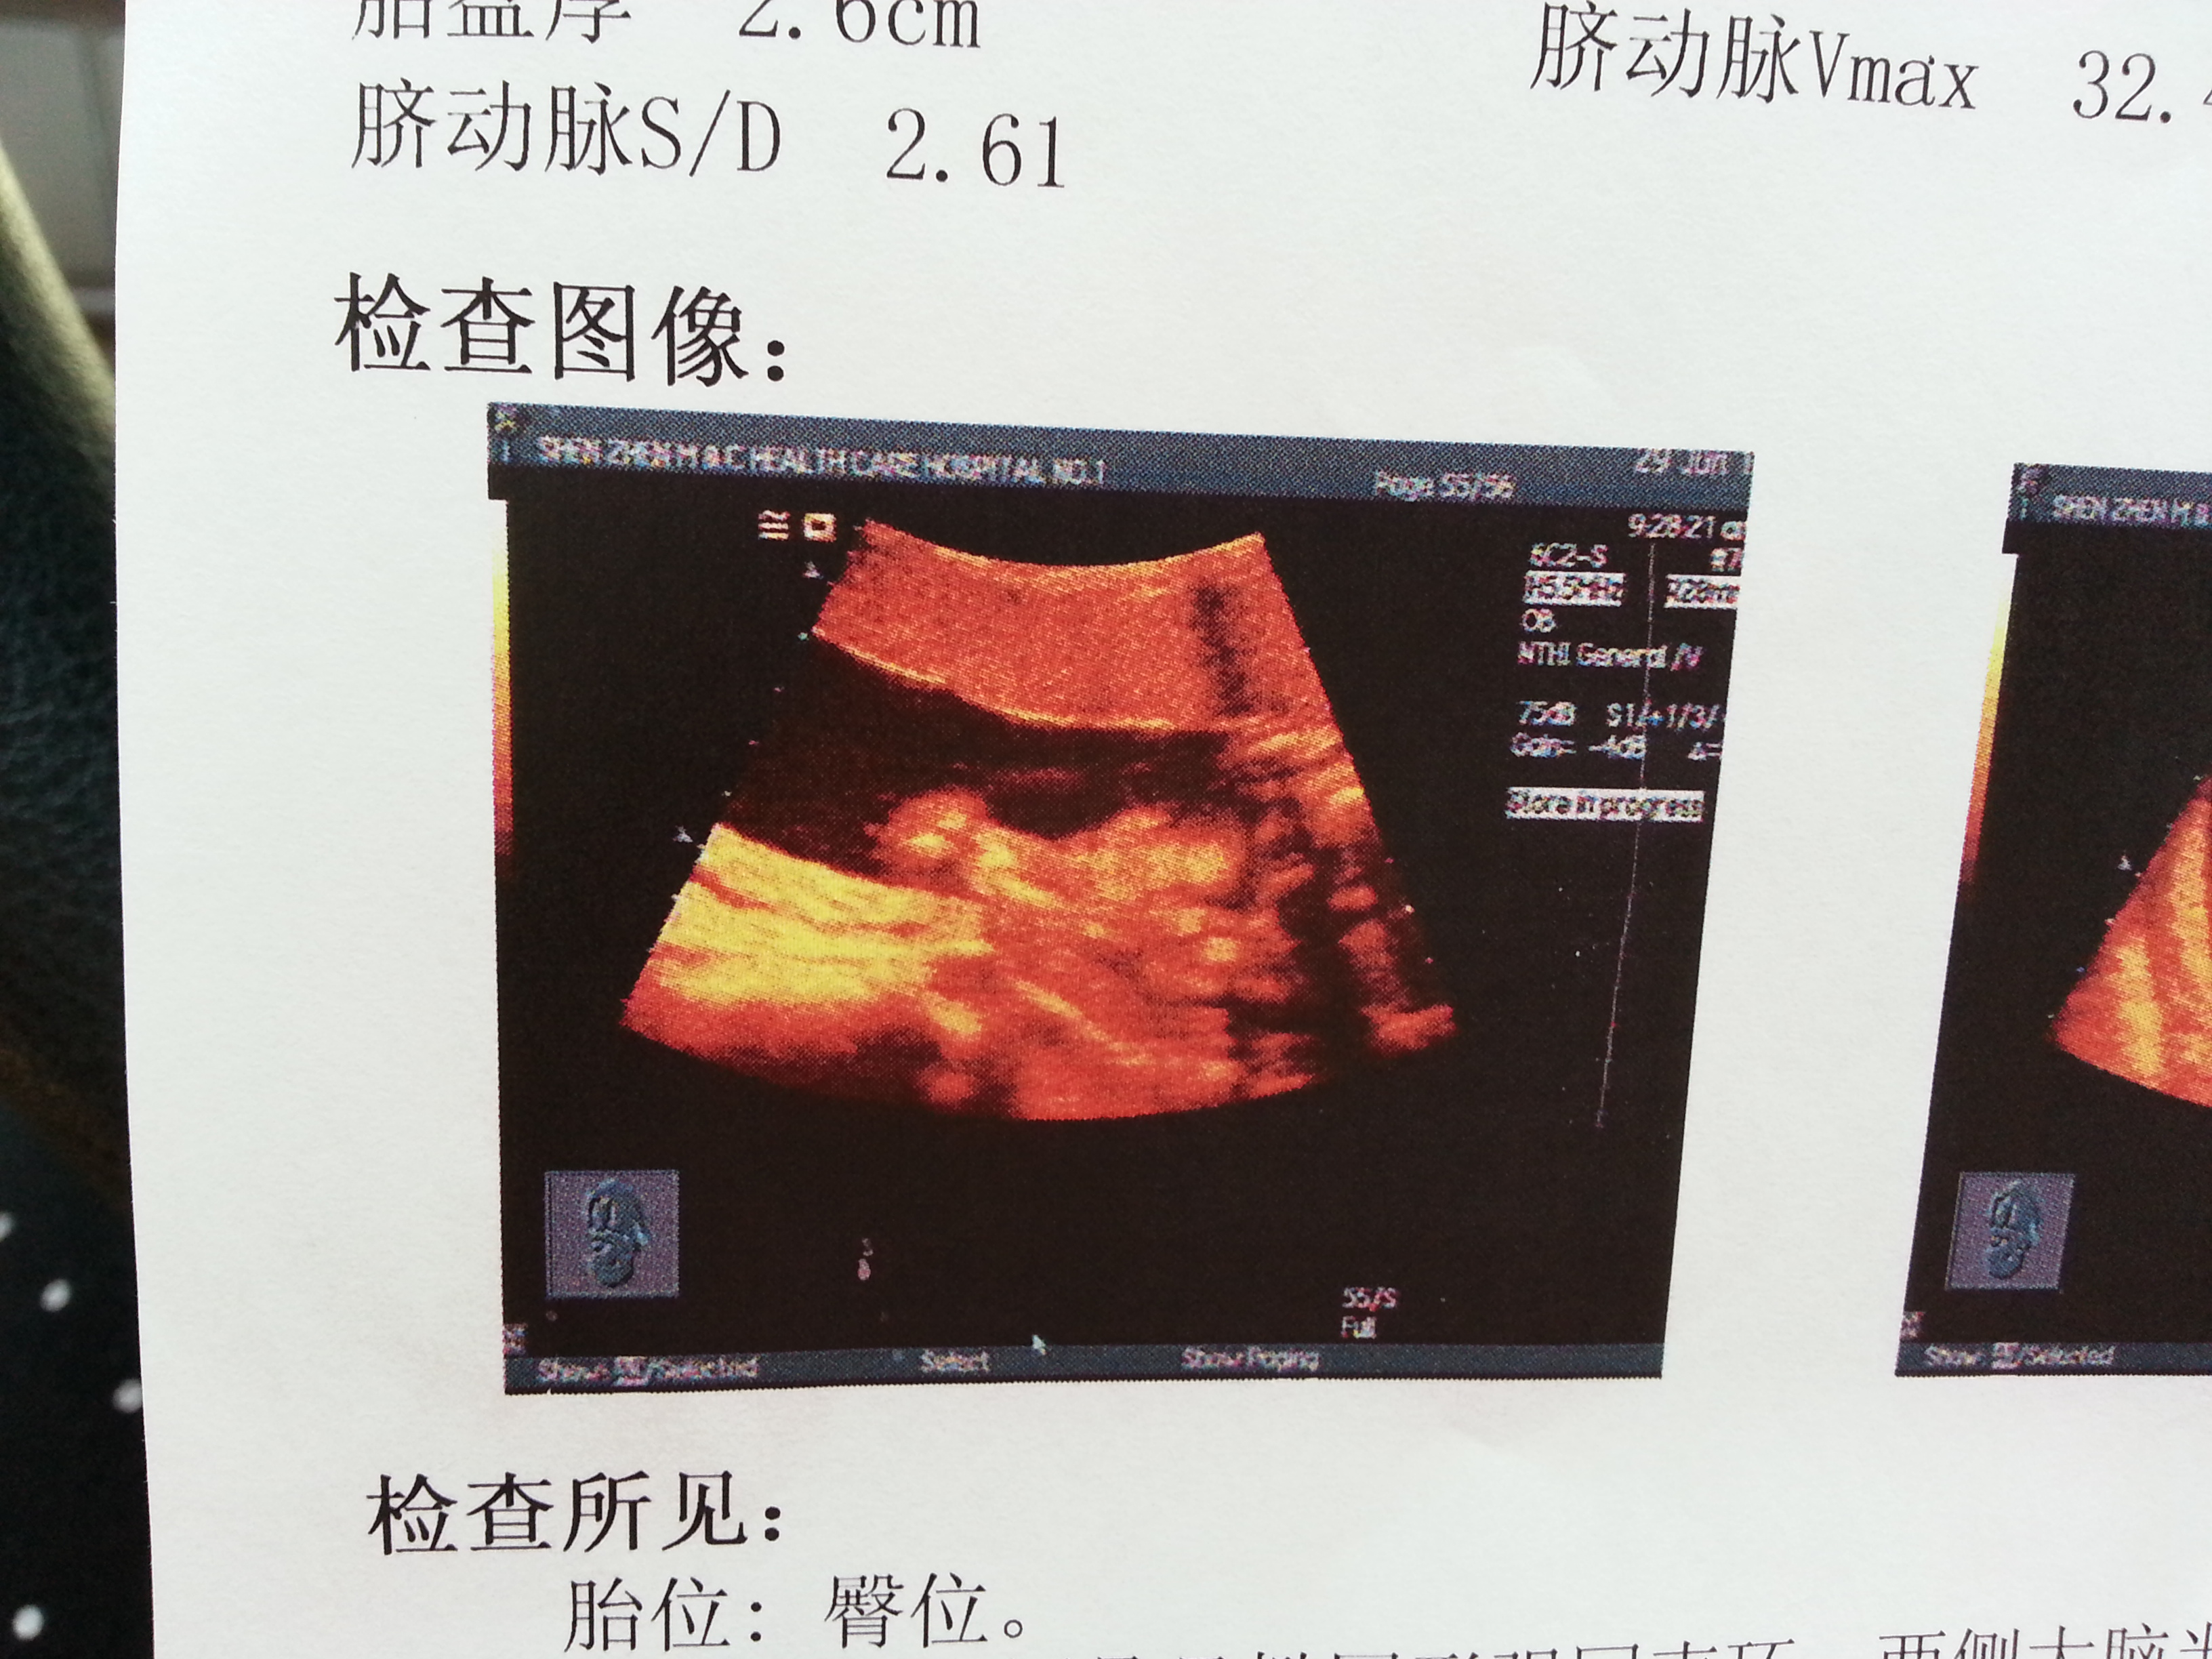

为什么你们的都有显示宝宝的脸,我的是啥图呀?

你照的不是三维和四维吧。。

产科三级彩超,是三维吗?

这三张图是啥?